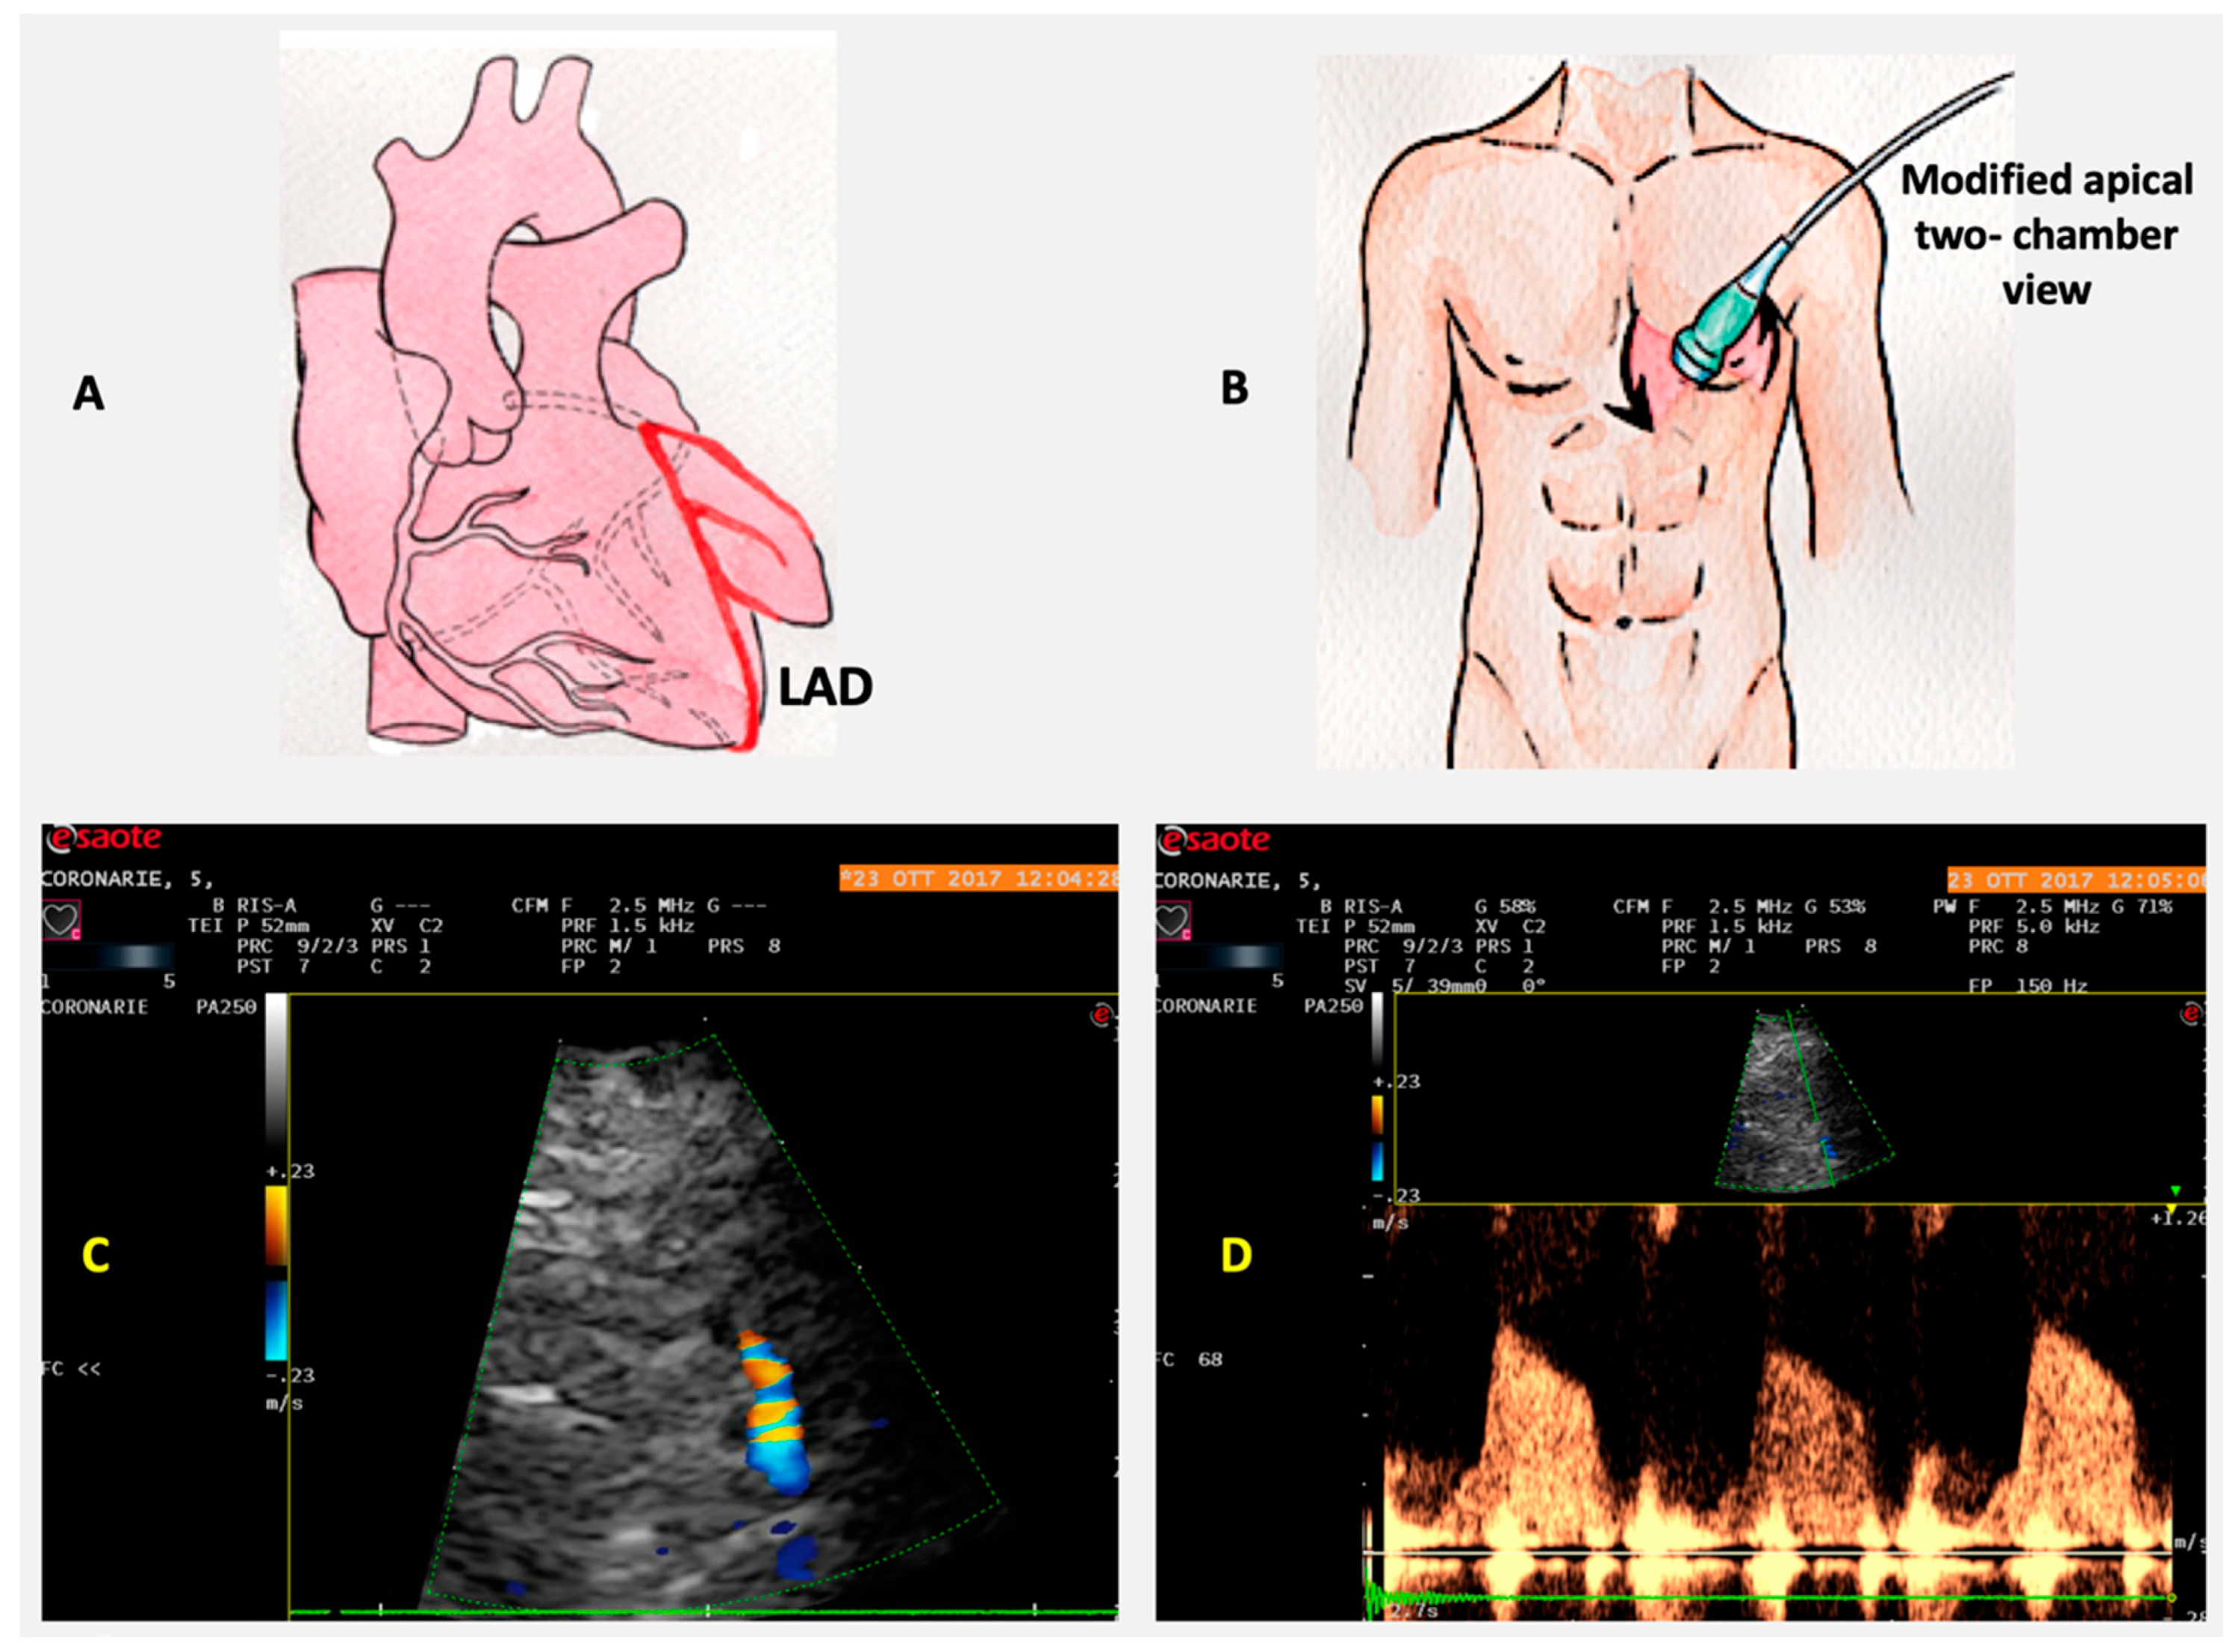

6. Coronary Flow Reserve

Role of CFR in IHD